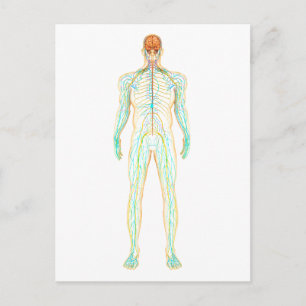

Cartão Postal Poster de conexão

Preço1,93 €